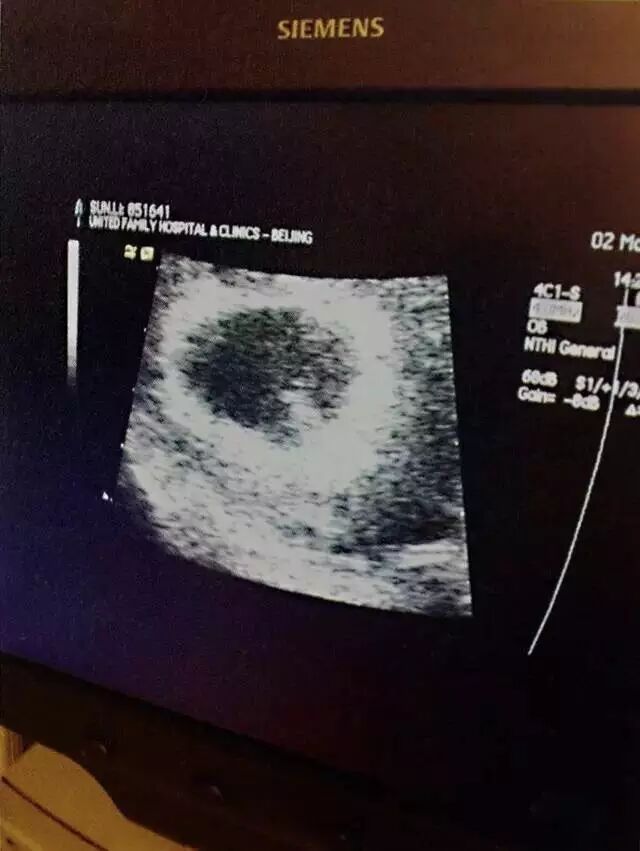

两个人都怀孕了

妹妹人儿就要来了

2013年12月,妹妹降生,从那一刻起,我们踏上新旅程。从此,一家四口啦!